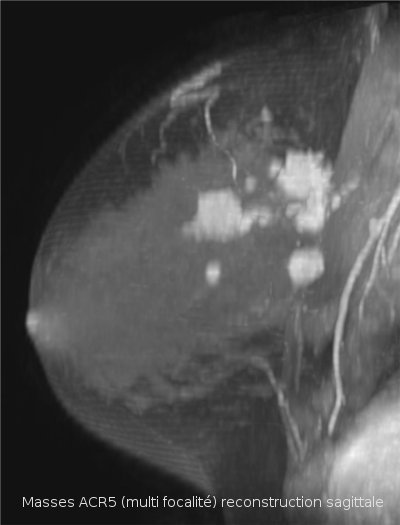

La morphologie de la lésion observée et la visualisation d'une ou plusieurs zones prises de contraste sont les principales informations fournies par l'IRM.

Une image de morphologie irrégulière surtout, et une prise de contraste associée avec courbe de type 5 (prise de contraste précoce, rapide et intense avec phase de lavage secondaire appelée "wash-out") oriente avec une probabilité d'environ 80% vers une lésion maligne (cancer). Selon le contexte médical la morphologie et l’aspect des prises de contraste des lésions peuvent traduire certaines pathologies du sein, notamment de nature cancéreuse.

- si une lésion cancéreuse volontiers multifocale ou bilatérale (cancer de type lobulaire par exemple) a été diagnostiquée, pour rechercher une autre lésion non décelée par la mammographie avec échographie.